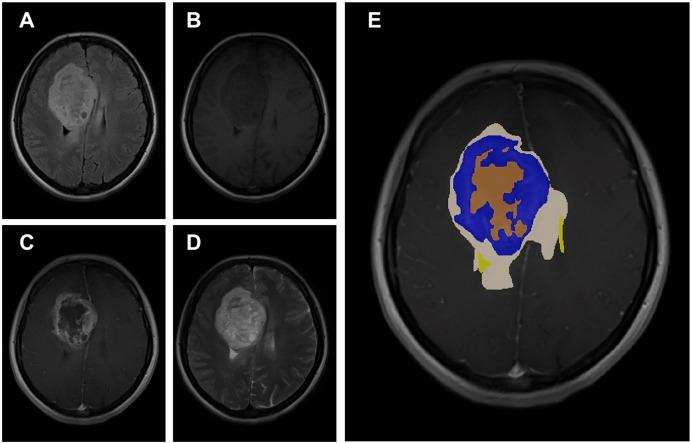

This article presents a new benchmark MRI dataset called the Gazi Brains Dataset 2020, containing MRI images of 100 patients, and introduces initial experimental results performed on this dataset in comparison with available brain MRI datasets. Furthermore, the dataset is analyzed using eight different deep learning models for high-grade glioma tumor prediction, classification, and detection tasks. Additionally, this study demonstrates the results of an explainable Artificial Intelligence (XAI) approach applied to the trained models. To demonstrate the utility of the proposed dataset, different deep learning models were applied to the problem, and these models were tested on various data and models applied for various tasks such as region of interest extraction, whole tumor segmentation, prediction, detection, and classification with accuracy, precision, recall, and F1-score. The experimental results indicate that the dataset is highly effective for multiple purposes, and the models reached significant results with successful F1-scores ranging between 93.2% and 96.4%. ROI and whole tumor segmentations were successfully performed and compared with seven algorithms with accuracies of 87.61% and 97.18%. The Grad-CAM model also demonstrated satisfactory accuracy across the tests that were conducted. Moreover, this study explores the application of XAI to the trained models, providing interpretability and insights into the decision-making processes. The findings signify that this dataset holds significant potential for various future research directions, including age estimation, gender detection, causal inference with XAI, and disease-related survival analysis.

本文介绍了一个名为2020年加济大脑数据集的新的基准MRI数据集,其中包含100名患者的MRI图像,并介绍了与现有脑MRI数据集相比在该数据集上进行的初步实验结果。此外,使用八种不同的深度学习模型对该数据集进行分析,以完成高级别胶质瘤肿瘤的预测、分类和检测任务。此外,本研究展示了将可解释人工智能(XAI)方法应用于训练模型的结果。为了证明所提出数据集的实用性,将不同的深度学习模型应用于该问题,并在各种数据和模型上对这些模型进行测试,这些数据和模型用于各种任务,如感兴趣区域提取、全肿瘤分割、预测、检测和分类,并计算其准确率、精确率、召回率和F1分数。实验结果表明,该数据集在多个方面都非常有效,模型取得了显著成果,F1分数成功达到93.2%至96.4%。成功进行了感兴趣区域和全肿瘤分割,并与七种算法进行了比较,准确率分别为87.61%和97.18%。Grad-CAM模型在进行的测试中也表现出令人满意的准确率。此外,本研究探索了将XAI应用于训练模型,为决策过程提供了可解释性和见解。研究结果表明,该数据集在包括年龄估计、性别检测、利用XAI进行因果推断以及疾病相关生存分析等各种未来研究方向上具有巨大潜力。